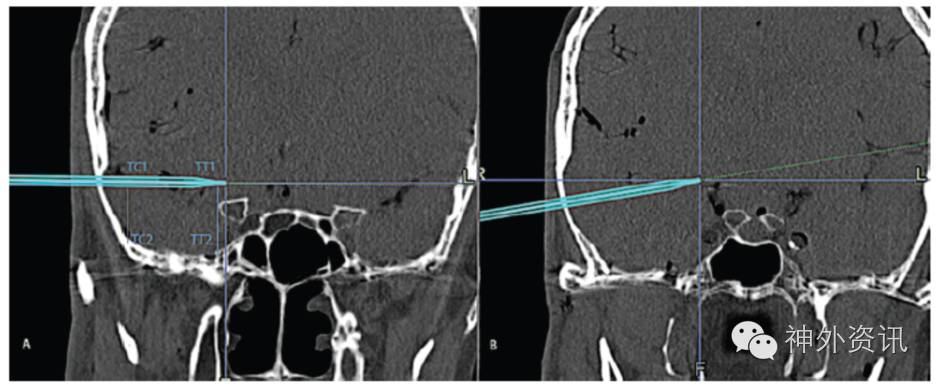

尸头每一侧均同时进行标准颞下入路和锁孔入路。显微镜下,用带有导航功能的探针定位尸头标本上的目的点,通过导航软件计算坐标和两点间距离。测量以下解剖学指标:①颞叶牵拉程度:外侧距离为骨窗处将脑牵拉向中点至同水平颅底骨质的垂直距离,内侧距离为四边形的目标区域处将脑牵拉向中点至同水平颅底骨质的垂直距离(图3);②解剖通道的容积:在目标区域的四边形范围内用棉片保护,然后往颞叶下方的解剖通道内灌注液态塑脂,待塑脂凝固后测量其体积;③手术通道容积:手术通道为手术器械在目标区域上可自由移动的空间范围,大致为一个圆锥体,底为目标区域,顶为骨窗处的暴露面积;④操作角度(angle of attack):在骨窗下缘与目标区域上缘作连线,骨窗上缘与目标区域下缘作连线,两线交角为垂直角度;骨窗前缘与目标区域后缘作连线,骨窗后缘与目标区域前缘作连线,两线交角为水平角度。

图3. 测量颞叶牵开的外侧和内侧距离。A.未离断颧弓时,颞叶牵开程度的测量;B.离断颧弓后颞叶牵开程度的测量。